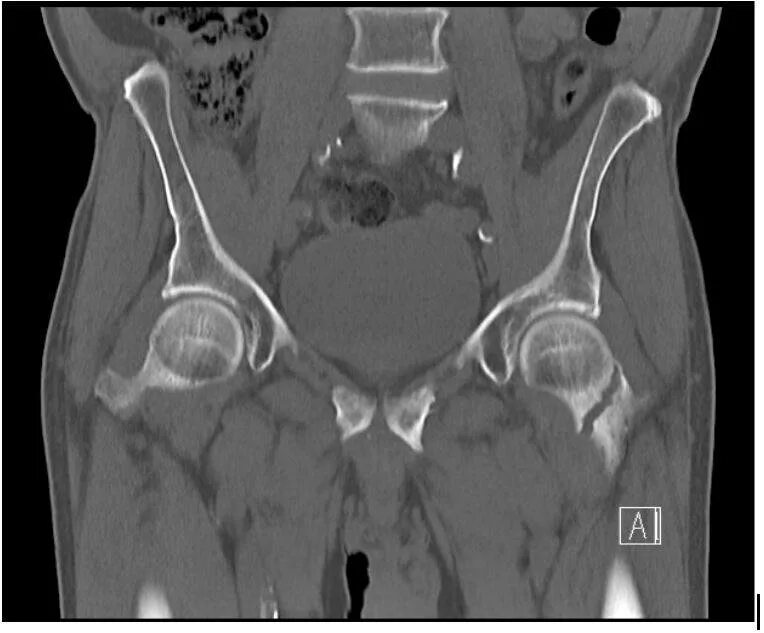

Кт суставов что показывает